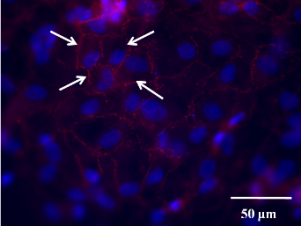

After the successful construction of an ECM-like scaffold, primary human aortic endothelial cells (HAECs) were used to evaluate the scaffold's biocompatibility and its capacity to support the regeneration of a functional endothelium. Our results show that HAECs could easily adhere to the scaffold's luminal surface and form a confluent mono-layer within 24 hr, given an appropriate seeding concentration. In addition, tight junctions between adjacent HAECs were detected within the same time window. This endothelial mono-layer almost completely prevented human platelet adhesion while the bare scaffold induced widespread platelet adhesion and aggregation.

Fig.3 From left to right: HAECs confluent mono-layer; Tight junctions (white arrows) between adjacent HAECs; Platelet adhesion and aggregation on bare scaffold; Platelet adhesion on exposed scaffold (white arrows) in an endothelial mono-layer. No platelet adhesion/aggregation on HAECs mono-layer.